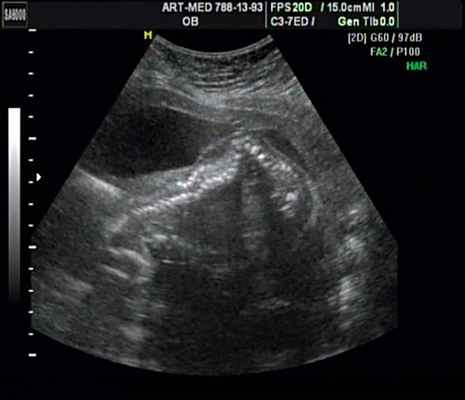

В первые часы жизни ребенок доставлен в отделение реанимации и хирургии новорожденных НИИ детской хирургии НЦЗД РАМН. Проведена компьютерная томография (КТ) с внутривенным контрастированием и магнитно-резонансная томография (МРТ) пояснично-крестцового отдела позвоночника. Данные МРТ: в крестцовом отделе позвоночника имеется четыре позвонка на уровне позвонков SII-SIV, позвоночный канал деформирован, отсутствуют остистые отростки позвонков, имеется дефект канала на уровне позвонка SII, через который пролабируют оболочки спинного мозга. Размер грыжевого выпячивания 14×14×9 мм, содержимое - спинномозговая жидкость (рис. 2).

Беременная М., 21 года. Впервые обратилась в клинику в срок 20 нед беременности. Исследование проводилось на аппарате SonoAce-R7 (Samsung Medison) с использованием режима поверхностной объемной реконструкции 3D/4D. При изучении позвоночника плода в трех плоскостях костных деформаций не выявлено. В грудном отделе позвоночника обнаружено тонкостенное кистозное образование с анэхогенным содержимым, стебельчатой формы (рис. 10-12). Степень "прозрачности" содержимого была выше околоплодных вод, что позволяло идентифицировать его как ликвор. В проекции грыжевого выпячивания располагалась петля пуповины, дифференциальную диагностику которой без труда удалось провести с помощью ЦДК (рис. 13).

Рис. 11. Беременность 20 нед. Менингоцеле.

Рис. 12. Менингоцеле. В сагиттальном срезе видна неровность кожи в проекции расщелины.